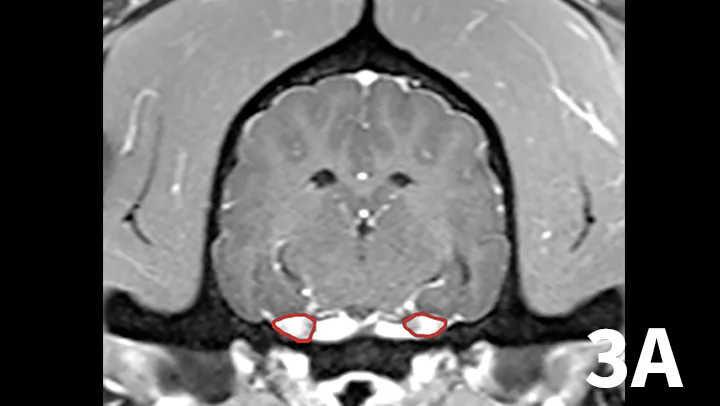

3. Trigeminal Neuritis and Idiopathic Trigeminal Neuropathy

A range of infectious and noninfectious inflammatory diseases can affect peripheral nerve branches. The most frequently recognized inflammatory entity in dogs affecting peripheral branches of cranial nerves is trigeminal neuritis or idiopathic trigeminal neuropathy (ITN).5 Affected dogs typically have an acute onset of clinical signs secondary to bilateral motor branch dysfunction of the trigeminal nerves. This bilateral involvement of the trigeminal nerve results in inability to close the mouth (drop jaw), difficulty prehending food, and drooling.5 About 33% of dogs have sensory involvement of the trigeminal nerve, and <10% have Horner syndrome or facial nerve dysfunction.5 While the underlying pathogenesis of this disease is not known, it is believed to be noninfectious and inflammatory in origin.5 Other causes can be excluded via MRI and cerebrospinal fluid analysis. Reported MRI findings include bilateral, subtle enlargement of the trigeminal nerve with associated T2 hyperintensity (Figure 3).2 The reported mean time to recovery is 22 days with <10% of dogs taking >6 weeks to recover.5 No treatment beyond assisted feeding is recommended for ITN. It may be necessary to try several food consistencies to determine what will be easiest for a particular dog to prehend; rarely, feeding tubes may be necessary. Team members who handle dogs (or cats) with any acute neurologic disease process, especially involving the trigeminal nerves or lower motor neuron system, should wear gloves, as rabies is a differential diagnosis, especially in unvaccinated animals.

Transverse postcontrast T1WI at the level of the caudal thalamus from a normal dog (A) and a dog with trigeminal neuritis (B). The trigeminal nerves are outlined in each study in red. The dog with trigeminal neuritis has grossly enlarged trigeminal nerves without an overt, identifiable mass.